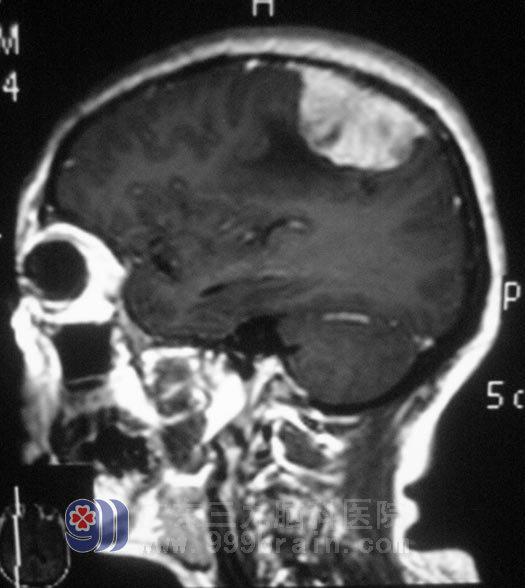

在广东三九脑科医院进一步检查,头颅MR检查提示右侧额顶部占位性病变,大小约4.3cm×4.2cm×2.2cm,考虑脑膜瘤。综合神经外科 鲁明主任为王女士在全麻下行右侧额顶部脑膜瘤切除术,术中切开硬脑膜后,显微镜下见肿瘤与硬膜粘连紧密,位于额顶部,肿瘤部分呈灰白色,质地、血运一般,与脑组织边界较清,予肿瘤全切。术后王女士没有出现肢体偏瘫等不良并发症。术后经病理证实为:合体型脑膜瘤。

▲手术前